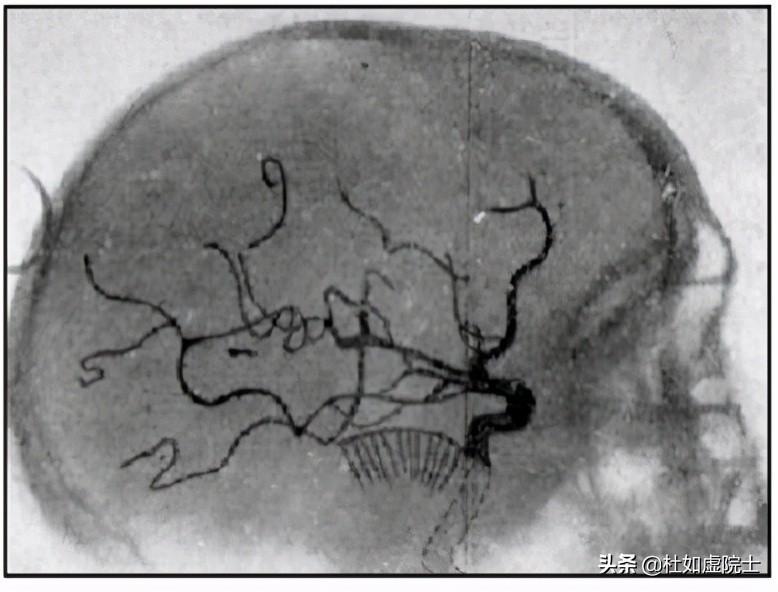

1927年,葡萄牙醫(yī)生安東尼奧·伊加斯·莫尼茲(Antonio Egas Moniz,1874—1955)發(fā)明了用X射線觀測(cè)腦血管的血管造影技術(shù)。莫尼茲是個(gè)特殊人物。1902年,他獲得醫(yī)學(xué)博士學(xué)位后不但行醫(yī),而且從政,曾任葡萄牙的外交部長(zhǎng)。1926年,他離開(kāi)了政界,到里斯本大學(xué)任神經(jīng)科教授。翌年,他開(kāi)發(fā)出了血管造影的技術(shù)(圖6)。這一技術(shù)的關(guān)鍵是在動(dòng)脈注入顯影劑,當(dāng)顯影劑隨血液流過(guò)大腦時(shí)用X光進(jìn)行分析。1936年,他又發(fā)明了用前額葉皮層切除術(shù)(Prefrontal leucotomy)調(diào)節(jié)大腦神經(jīng)的病變,卻導(dǎo)致了一些病人終身不能自理。其中的是約翰·肯尼迪(John F. Kennedy, 1917—1963)的妹妹Rosemary Kennedy。1949年,莫尼茲獲得了諾貝爾醫(yī)學(xué)獎(jiǎng)。同年他被他的一個(gè)病人開(kāi)槍打傷,只能坐在輪椅上。過(guò)了幾年就逝世了。莫尼茲還是作家,寫(xiě)過(guò)好幾本關(guān)于葡萄牙歷史人物的書(shū)籍,流傳至今。

圖6,安東尼奧·伊加斯·莫尼茲及他的血管造影術(shù)